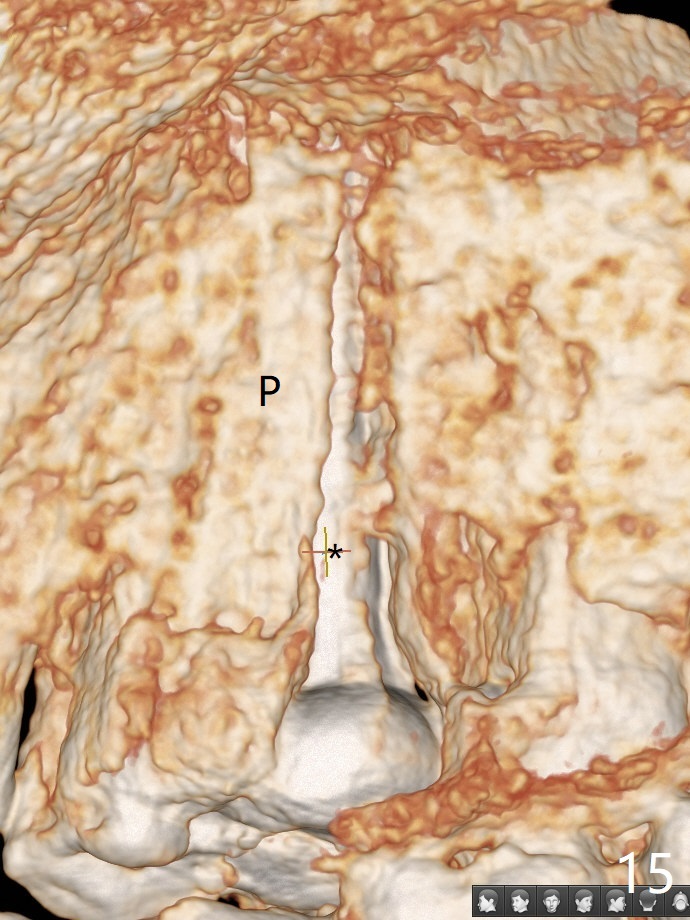

In fact there is a small buccal fistula, which is communicated with the underlying implant threads. Although preop CT shows that the buccal crest is lower than the palatal (3.8x13 mm, Fig.10 P) one, intraop finding of missing buccal plate should dictate a shorter implant (Fig.11) or onlay graft to avoid periimplantitis. Regeneration of the bone plate is limited. Later the fistula disappears with formation of a concavity (Fig.13). There is no symptom. Is bone graft necessary with a remote incision? 3-D images of CT taken 1 year 5 months post cementation show possible mesiobuccal and distopalatal bony defects (Fig.13-16). It is possible that bone graft was placed enough palatal (Fig.16). DO composite at #3 is redo satisfactorily (Fig.17 *).

Bone graft: 2 PRF membranes and 2 pieces of sticky bone buccal and palatal. Remove crown/abutment (incomplete seating) and place healing screw. Cover wound with Cytoplast and Acrylic dressing.